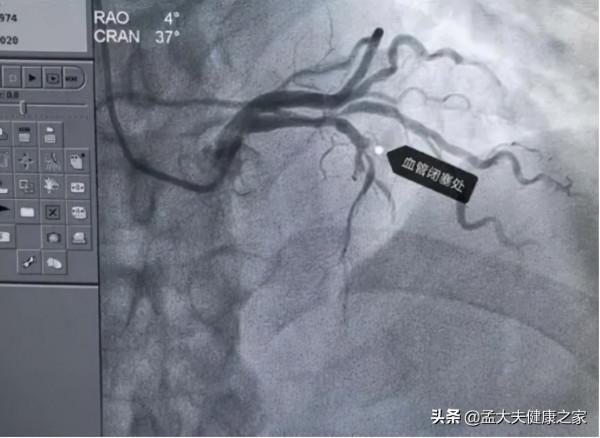

1.冠心病

冠心病是指冠狀動脈粥樣硬化性心臟病,主要是由於動脈血管發生動脈粥樣硬化病變而引起的血管堵塞,造成心肌缺血或壞死的一種心臟病。它具有發病快,不規律且危害大的特點,往往給患者造成過大的心理壓力。